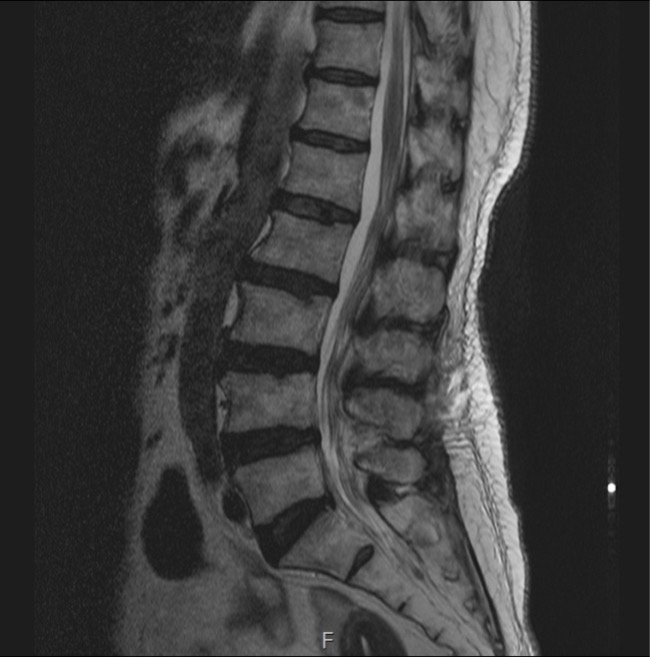

척추관협착증

척추관협착증이란

어떤 원인으로 척추 중앙의 척추관, 신경근관 또는 추간공이 좁아져 허리의 통증의 유발하거나 다리에 여러 복합적인 신경증세를 일으키는 질환

입니다.

디스크를 구성하는 수핵과 섬유륜에 퇴행성 변화가 일어나고 척추관을 구성하는 뼈와 인대 등이 두꺼워져 척추 뼈가 어긋나는 경우 척추 신경을 눌러 통증을 일으킵니다.

주요 원인과 증상

원인

· 노화로 인한 퇴행성 변화

· 척추에 무리가 되는 생활습관

· 외상으로 인한 척추 부분 손상

· 선천적 요인